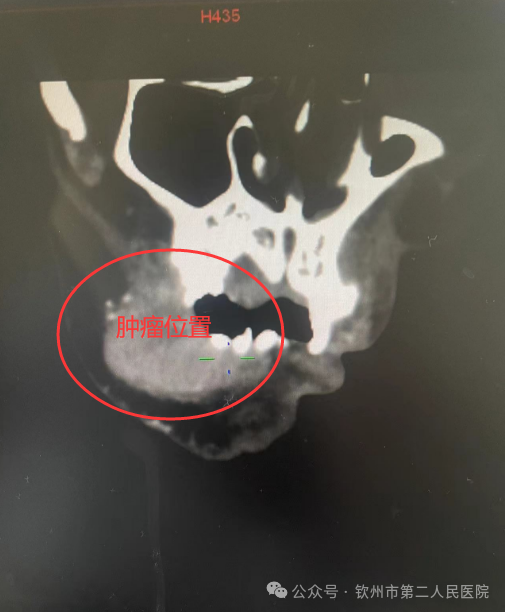

1个月前,62岁的程伯(化名)因右侧口颊粘膜长了巨大肿物出现反复口腔疼痛、张口受限,并出现反复出血。程伯来到我院耳鼻咽喉头颈外科二病区就诊,科主任吕忠对程伯的病情非常重视,立即对程伯的症状和体征进行详细分析,并完善了相关检查。肿物组织的病理检查回报:右侧口颊粘膜癌,CT提示肿瘤累及大部分右侧口颊粘膜。

为了尽量减轻程伯及家属的诸多顾虑,吕忠耐心详细的给他们讲解了手术的利与弊,最终程伯及家属同意手术。为了解决完整切除程伯口颊区肿瘤及修复封闭口颊区,手术团队针对程伯的病情结合术前CT、MRI等影像资料,对手术方案进行反复讨论和研究,最终选择行口颊粘膜癌扩大切除术+前臂游离肌皮瓣转移修复。由吕忠团队负责行肿瘤切除+颈淋巴结清扫,骨外科四区易广田主任团队同时制备前臂游离皮瓣,再由吕忠团队使用皮瓣塑形修复切除肿瘤后的口颊部内外面粘膜皮肤软组织的缺损。